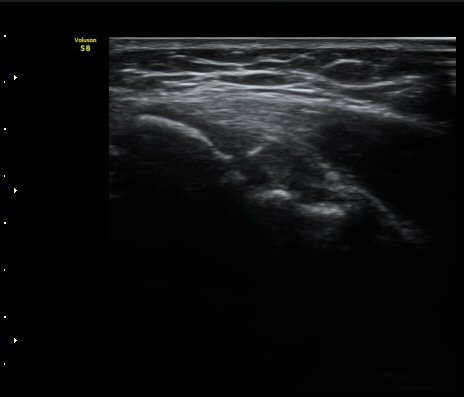

ÃÊÀ½ÆÄ °Ë»ç

³»»ó°ú Á¾´Ü¸é°Ë»ç»ó  ³»ÃøºÎÀδë Àú¿¡ÄÚ ºÎÁ¾°ú ³»»ó°ú ÀÎ´ë ºÎÂøºÎ ÇÇÁú°ñÀÇ ºÒ±ÔÄ¢º¯È­¿Í

°ñÆíÀÌ °üÂûµÇ°í(±×¸² 1, 2, 3, 4) ÀÌ·±¼Ò°ßÀº °ÇÃø°ú ºñ±³ÇÏ¸é ´õ¿í ¶Ñ·ÈÇÔ(±×¸² 5, 6).